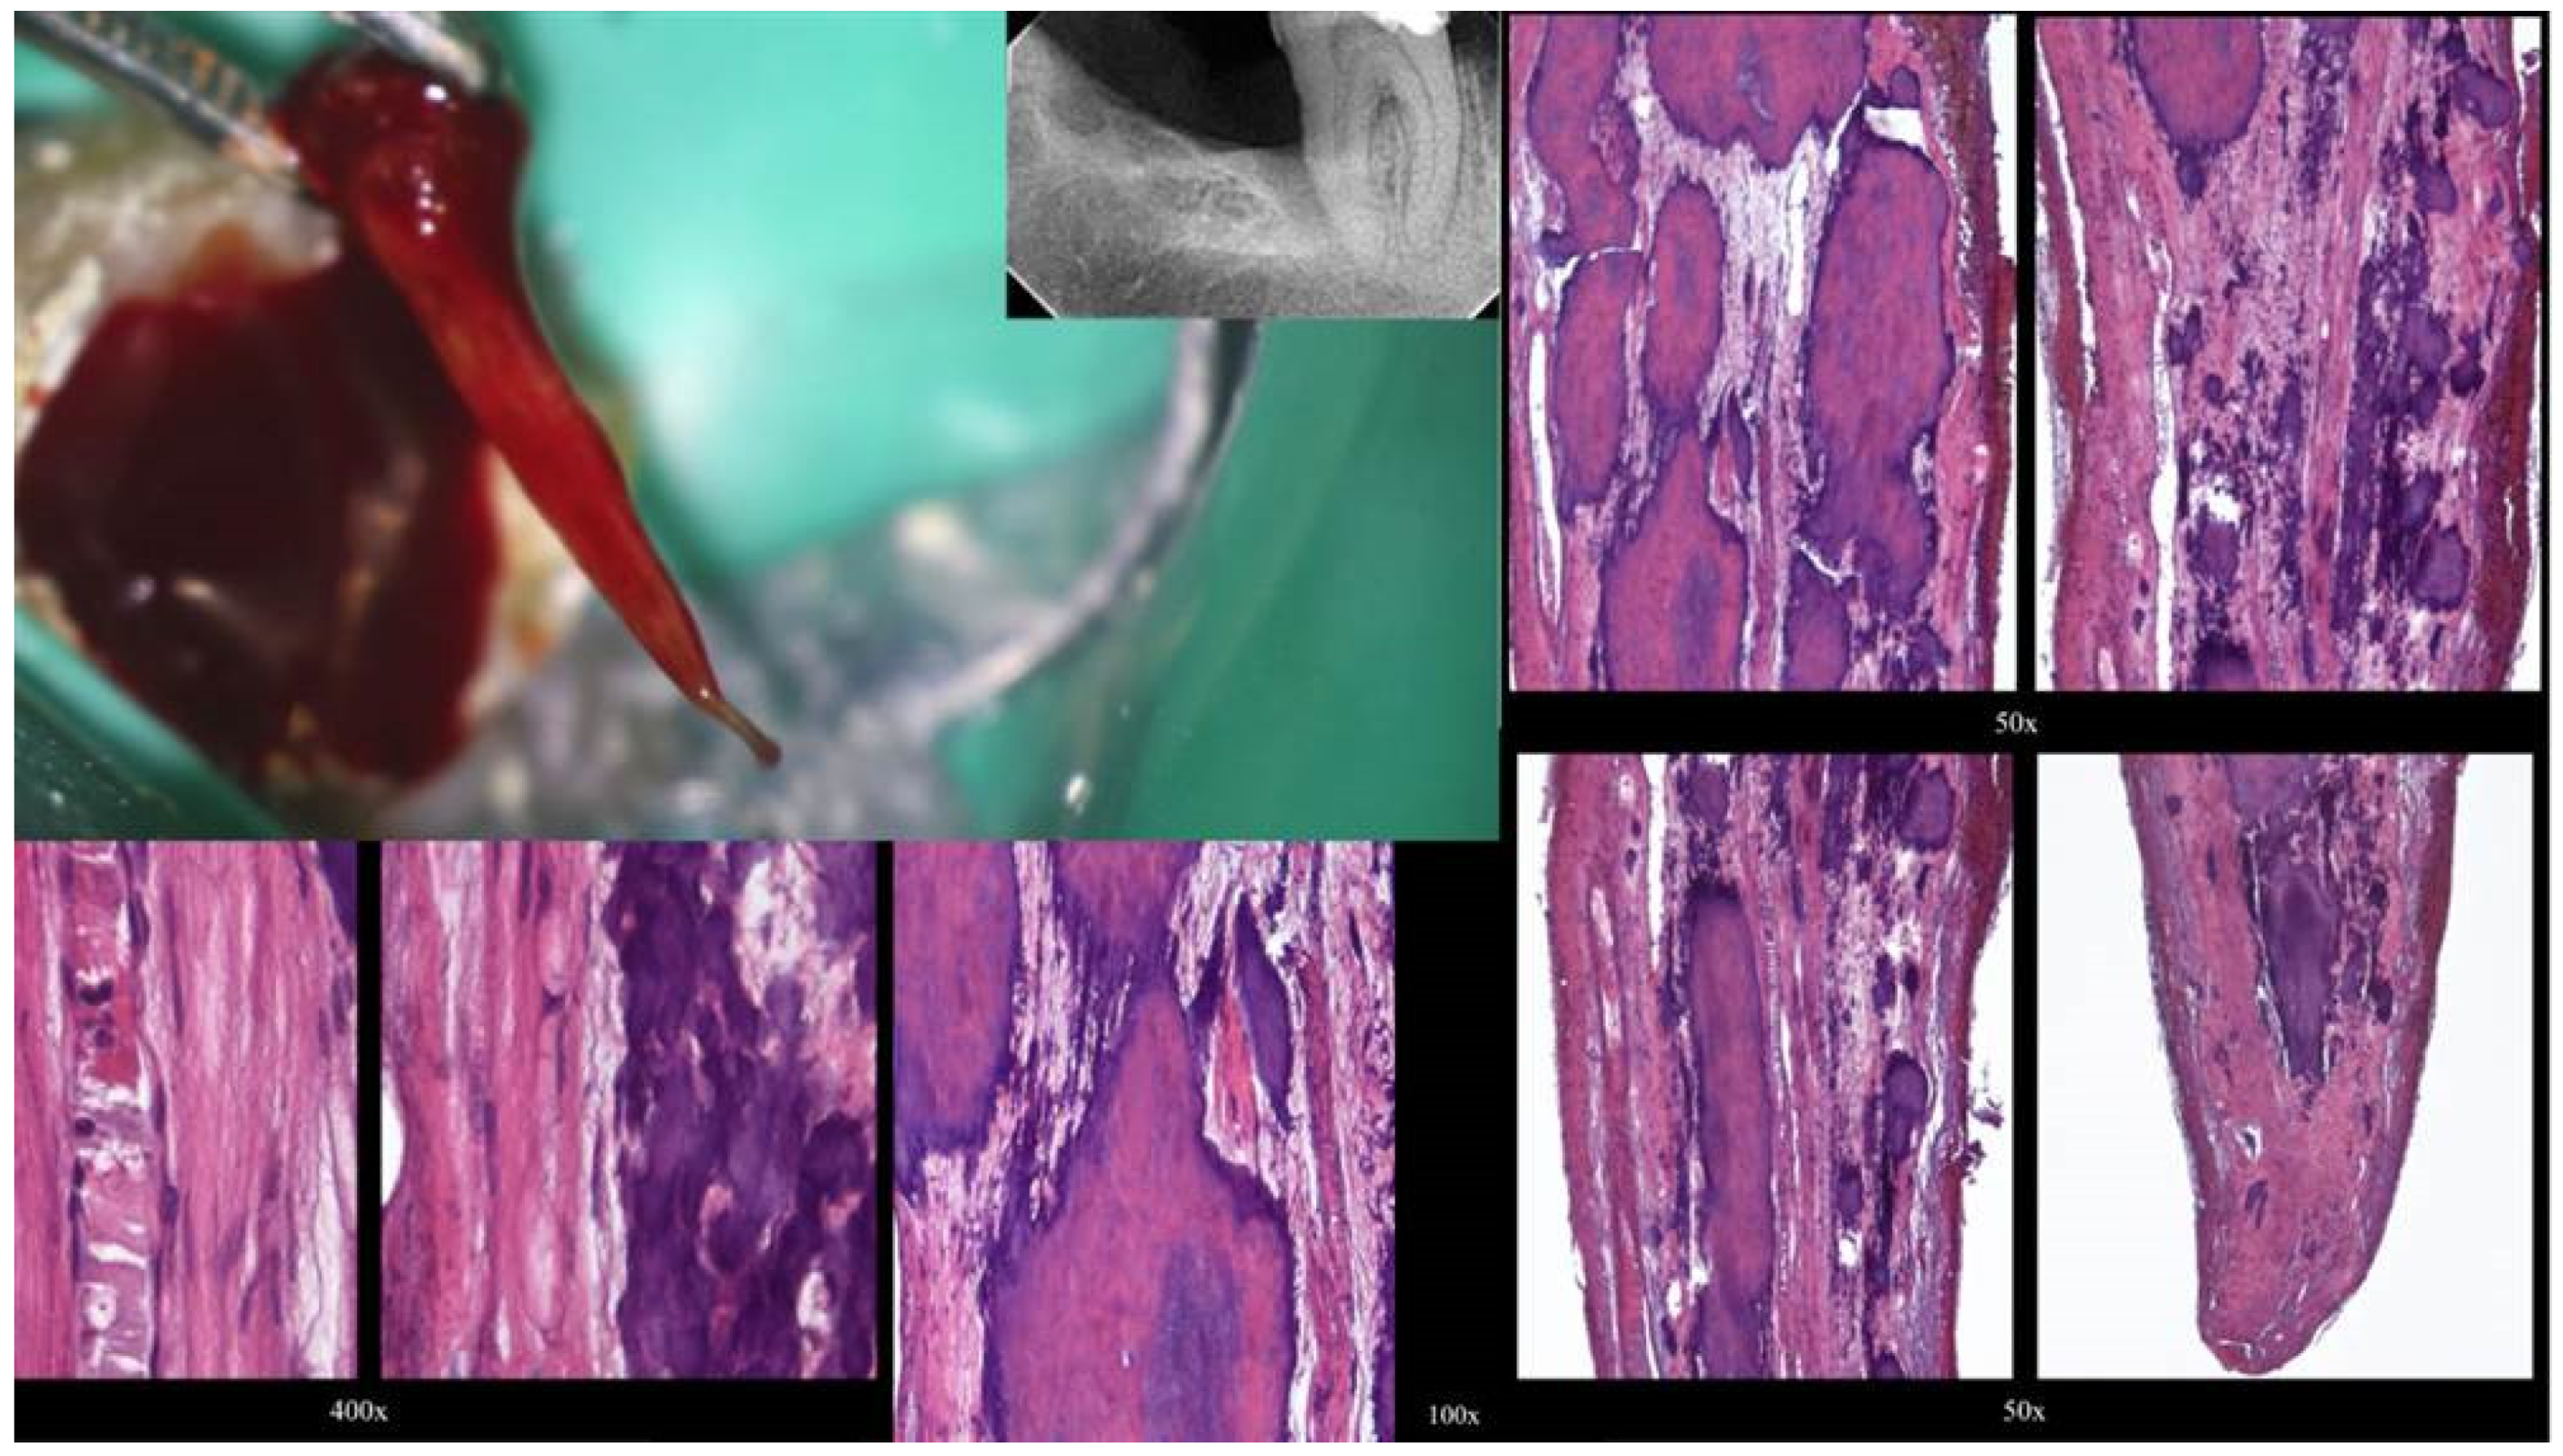

Figure 3.

Histological images of the calcified vital pulp tissue that was removed during the root canal treatment of a second mandibular molar with deep periodontal distal lesion suffering from symptomatic irreversible pulpitis. Notice the linear calcified nodules formed along the root pulp vessels (hematoxylin–eosin staining) (clinical and radiographic images are courtesy of Dr. Chaniotis Antonis, and histological images are courtesy of Prof. Domenico Ricucci).